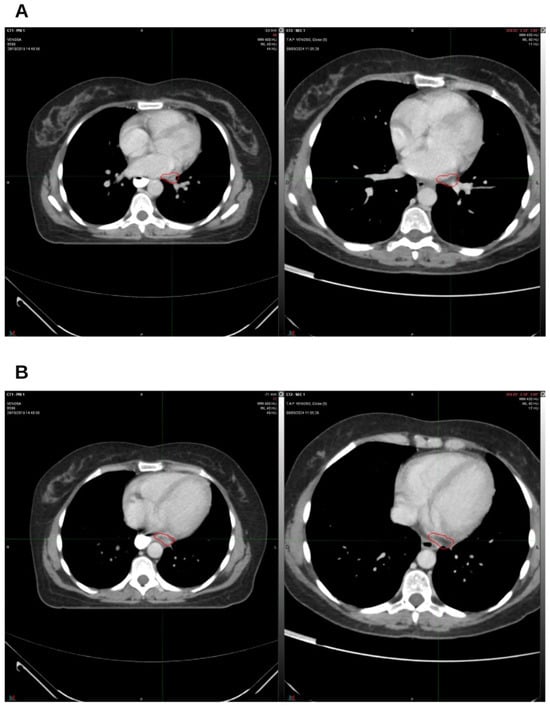

Integrative Use of Cannabidiol, Melatonin, and Oxygen–Ozone Therapy in Triple-Negative Breast Cancer with Lung and Mediastinal Metastases. A Case Report

Background and Clinical Significance: Breast cancer is the most frequent malignancy in women. Metastatic breast cancer is considered a treatable but incurable condition, with a median overall survival of only 2–3 years. Among its subtypes, triple-negative breast cancer (TNBC) accounts for a high proportion of breast cancer-related deaths. It is characterized by an aggressive clinical course, early recurrence, and a strong propensity for visceral and brain metastases. Case Presentation: We report the case of a Caucasian woman who developed systemic disease recurrence with lung and mediastinal lymph node metastases, occurring two years after her primary diagnosis and treatment for TNBC. The patient received three months of chemotherapy combined with an adjuvant integrative protocol consisting of melatonin, cannabidiol, and oxygen–ozone therapy. This combined approach led to the complete disappearance of the lung nodules. Subsequently, stereotactic radiotherapy was performed and, in association with the ongoing integrative treatment, resulted in a significant reduction in mediastinal adenopathy. Introduction of immunotherapy, supported continuously by the same adjuvant strategy, achieved a complete and durable remission. Strikingly, the patient remained disease-free five years after the diagnosis of lung and mediastinal metastases. Conclusions: This clinical case highlights the potential benefit of using melatonin, cannabidiol, and oxygen–ozone therapy as part of an integrative approach in patients with aggressive metastatic TNBC. While it is not possible to establish causality from a single case, the sustained remission observed suggests that such unconventional adjuvant strategies could play a supportive role in enhancing the efficacy of standard oncologic therapies. Full article

Figure 1